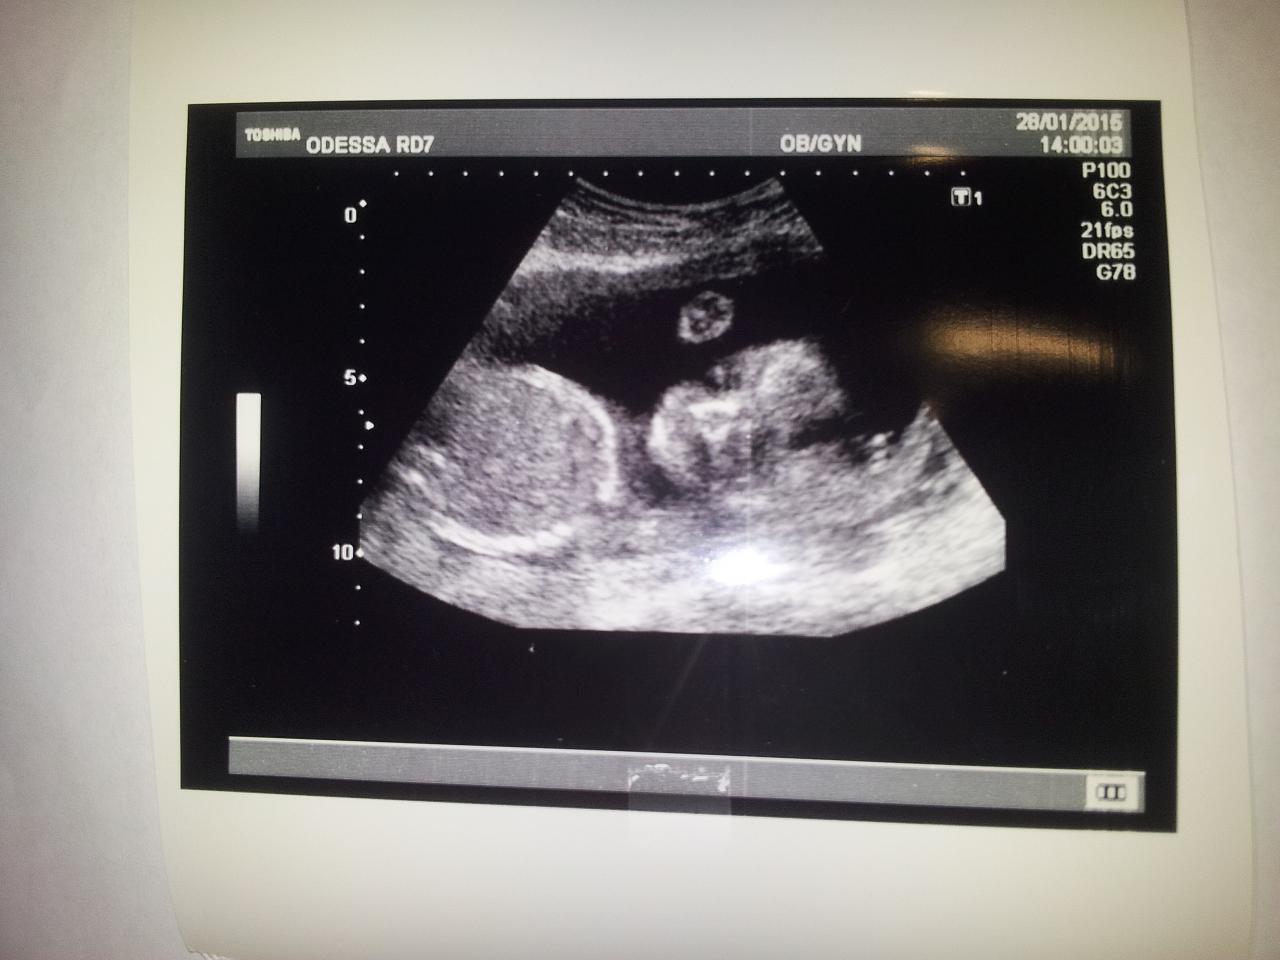

По этой причине - что хочу больше девочку, чем мальчика - не узнаю пол заранее. Хочу иметь во-первых стимул родить быстренько, чтобы узнать, и во-вторых, хочу спокойную и радостную беременность, пусть и в неведении. Готовлю себя и к тому и другому варианту, но месяцы до родов я буду счастлива от мысли, что у меня скорее всего девочка ))))) Вот даже по фото видно, что личико женское, да простят меня знатоки физиогномики.

Нажмите на изображение для увеличения

Название: 20150128_175814.jpg

Просмотров: 28

Размер:	91.3 Кб

ID:	9380101

Вложение 9380101

Да, больше на девочку похожа! Но! У нас Костю и сейчас девочкой называют а до года(до того как подстригли) вообще! Оссобенно врачи, ой какая девочка(глазки большие,ресници длинные и овал лица такой ну чисто девочка) так что))))

Цитата Сообщение от kiss_латинка Посмотреть сообщение

не ну что за глупости - точно ведь видно -девица-)))))))))))))))))))всем привет)